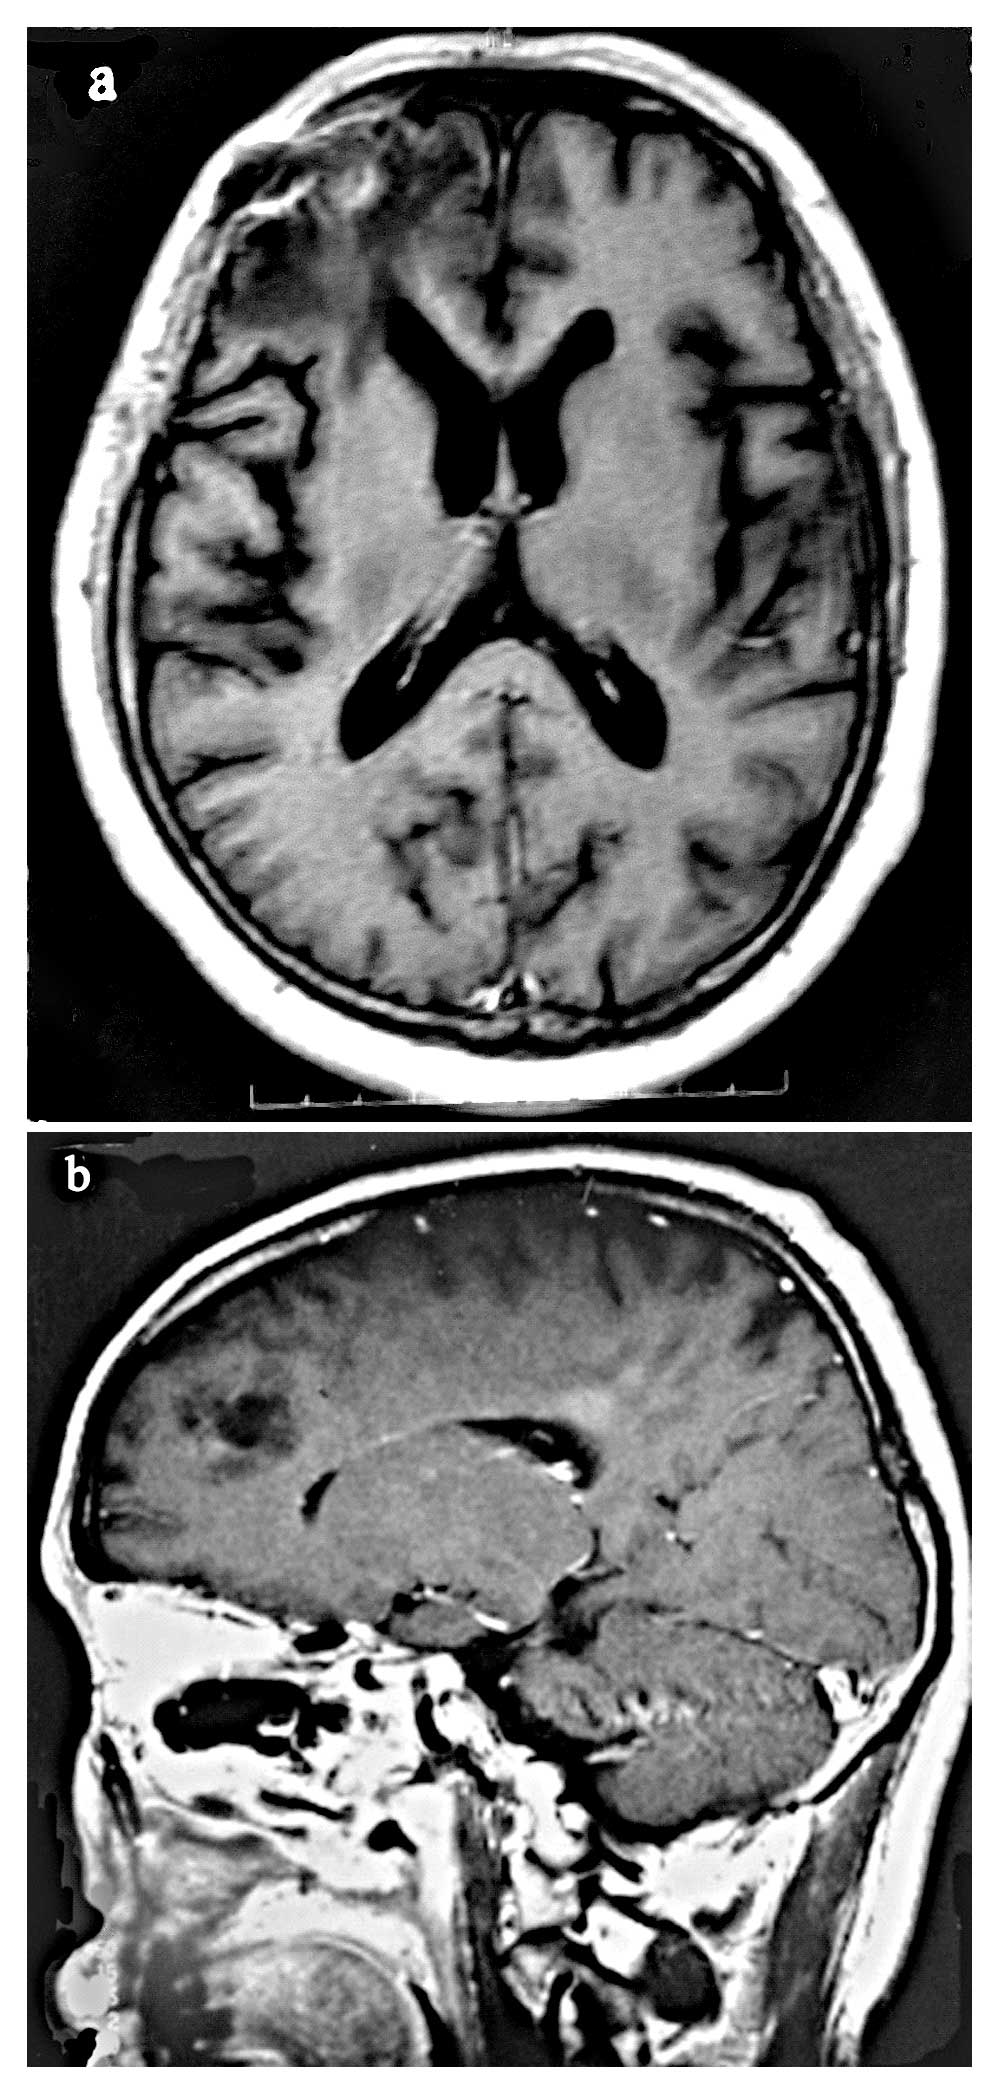

contrast-enhanced CT scan should be used. Relevant responses to

treatment may be assessed by neurological examination and by MRI

(Fig. 2A and B) or

contrast-enhanced CT scan following therapy, or during

follow-up.